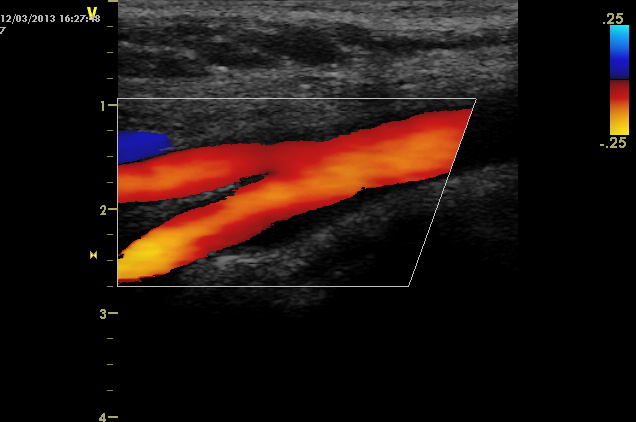

• Farbduplexsonographie der Becken- und Beinaterien

• Farbduplexsonographie der extrakraniellen hirnversorgenden Gefäße mit ITM-Bestimmung

Farbduplexsonographie der Becken- und Beinaterien